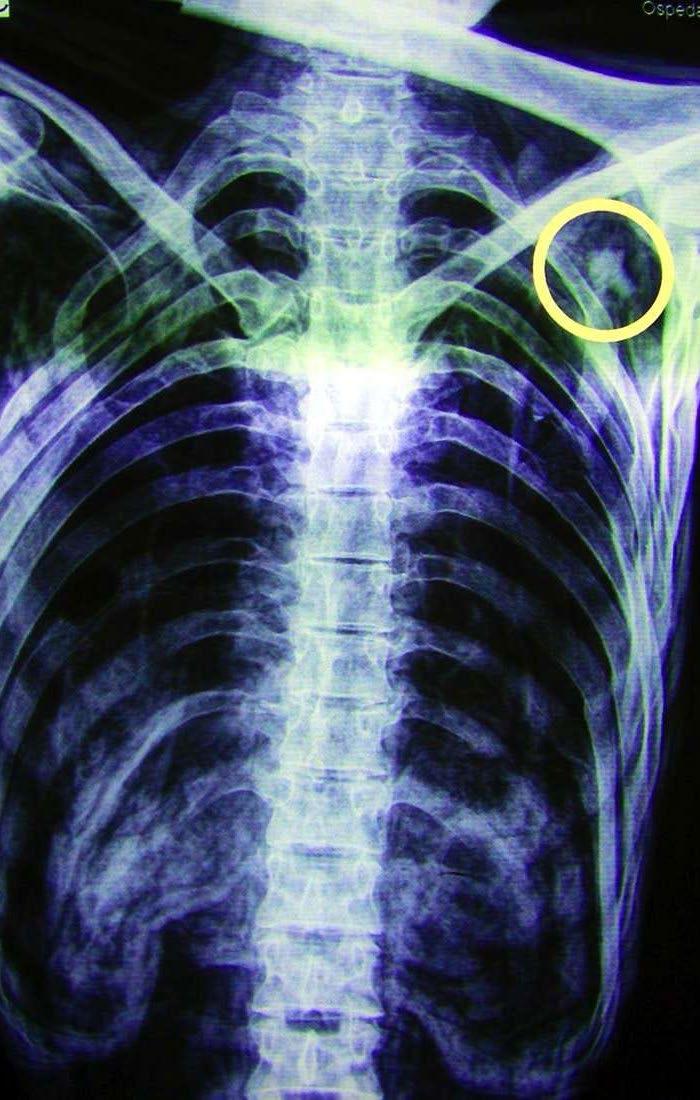

Radiografia com a flecha no ombro de Ötzi

Rastros de sangue de outras quatro pessoas estavam presentes em sua faca, dois na mesma flecha e um no casaco. Não foi um final dos mais simpáticos. Não. Um desentendimento por razões desconhecidas lançaram-no à morte. Com um metro e sessenta e cinco centímetros de altura, e entre trinta e quarenta e cinco anos de idade, Ötzi, assim chamado pelos pesquisadores, possuía sessenta e cinco tatuagens em seu corpo. Tudo foi possível de ser verificado graças à mumificação que o clima local impôs. Sorte e mais sorte.

Foi uma verdadeira festividade se depararem com tamanho achado, alguém tão antigo e tão bem conservado abrindo as portas aos necessários estudos que compreenderam desde a análise de tecidos até as radiografias que revelaram o provável motivo de sua morte naquele lugar do qual não saiu até a sua recente descoberta e preservação em Bolzano, cidade italiana que conta ainda com uma belíssima construção do século XIII, o castelo Mareccio, dentre outros prédios religiosos e de moradia e frondosos jardins.